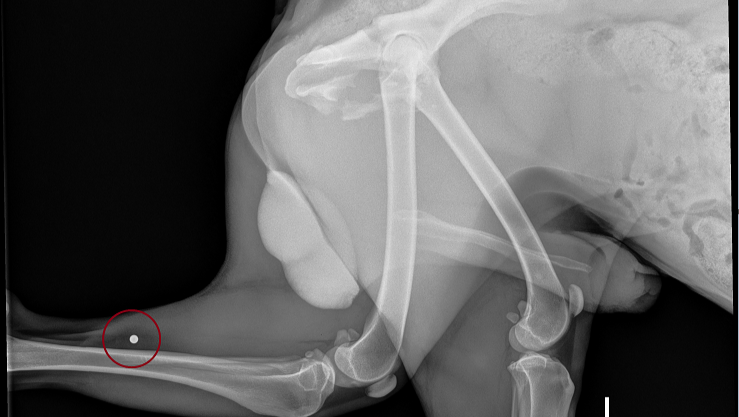

A Note from Wagster’s Foster Family: We don’t know what all happened to Wagster before the night he was found on Hwy 90, but we know it has not been an easy life. Along with his injuries from being hit by a car, X-rays revealed he had been shot multiple times with a BB gun. He also has several puncture wounds, so it appears he was in a dog fight before being hit by a car. He has heartworms, and we have started treatment. He started coughing the first night home, so he likely contracted kennel cough. On top of all of this, Wagster was whipped around so hard when he was hit that he can’t hear. Nobody knew he couldn’t hear because he engages with people so well. UPDATE Oct 6: His hearing is starting to come back! Hopefully, all of it will. Despite all he has been through, he is very sweet to everyone that he has encountered. He has not growled at all and waggles his tail at everyone he sees. UPDATE Oct 9: At first, Animal Control thought he was about seven years old because of the tartar build-up on his teeth, but with good nutrition and rest, his teeth look incredibly cleaner, so now they think he may be four or five years old.

Wagster is severely underweight AND had been shot multiple times. The veterinarian counted at least 5 BBs in him.

Wagster has a broken pelvic and broken femur (at the ball that goes into the hip). The ball at the top of the thighbone (femur) is called the femoral head.

Femoral Head Ostectomy vs. Hip Replacement: A break at the femoral head is a common injury seen in a dog hit by a car. Femoral Head Ostectomy is a standard surgery for small dogs. However, the surgery isn't always successful. The veterinarian removes the ball of the femur that goes into the hip, and then HOPES that enough scar tissue forms around the end of the cut off femur bone to create a "false joint." If this doesn’t work, the doggie is lame and in pain the rest of his life! For heavier dogs like Wagster, though, a hip replacement is the surgery of choice to enable him to run and play like before he was injured.